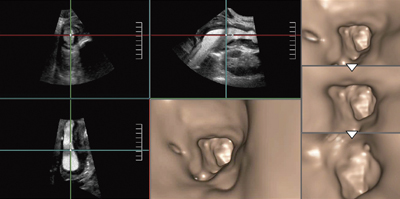

肝門部胆管がんの症例(図3)では,肝内胆管が拡張して肝門部に腫瘍がある。3D画像で胆管内を末梢から腫瘍に向かって視点移動することで,門脈浸潤の有無や,圧排か浸潤かなどの胆管と腫瘍との関係を,MPR画像と対比して観察することができた。

図3 肝門部胆管がんのFly Thru画像(末梢胆管→腫瘍へ)

個々の胆管や門脈と腫瘍との関係をMPR画像との対比で

より把握しやすい。